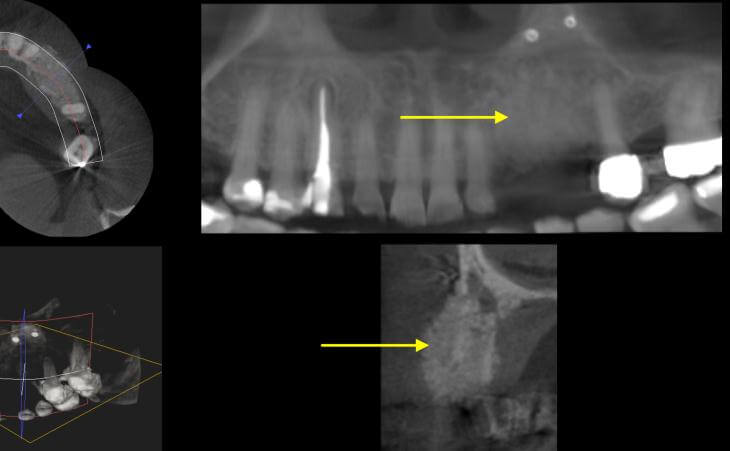

Resorbed Ridge Treatment Before Resorbed Ridge Treatment After

Resorbed Ridge Treatment After -

Pre surgical ct scan showed severely resorbed jaw bone After 4 months - a CT scan shows amazing bone volume regenerated

After 4 months - a CT scan shows amazing bone volume regenerated  Newly grown bone on CT scan

Newly grown bone on CT scan